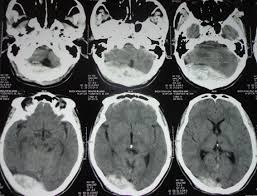

Hỏi bệnh sử và khám thực thể. Xét nghiệm máu, xét nghiệm gen, xét nghiệm đông máu. siêu âm, Chụp CT scan.

Click vào ảnh để xem 4 hình ảnh minh họa